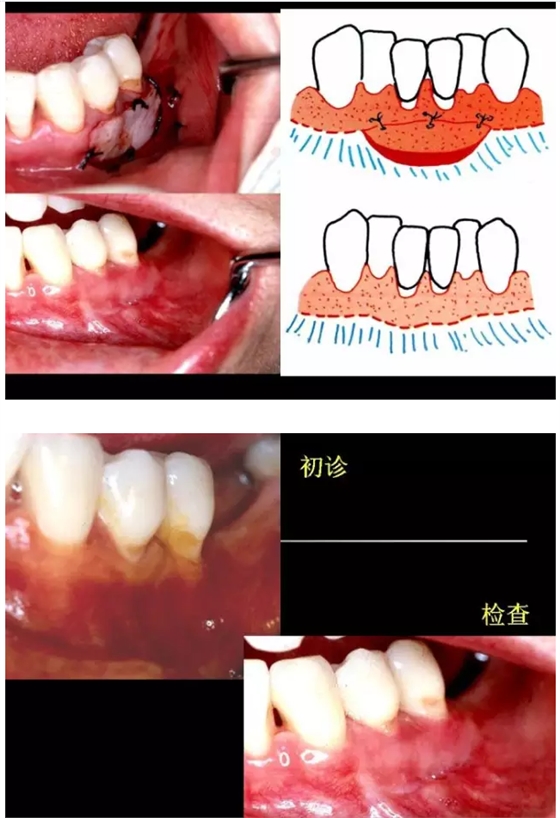

【牙科知識(shí)】牙周病相關(guān)手術(shù)圖解,非醫(yī)學(xué)專業(yè)勿點(diǎn)